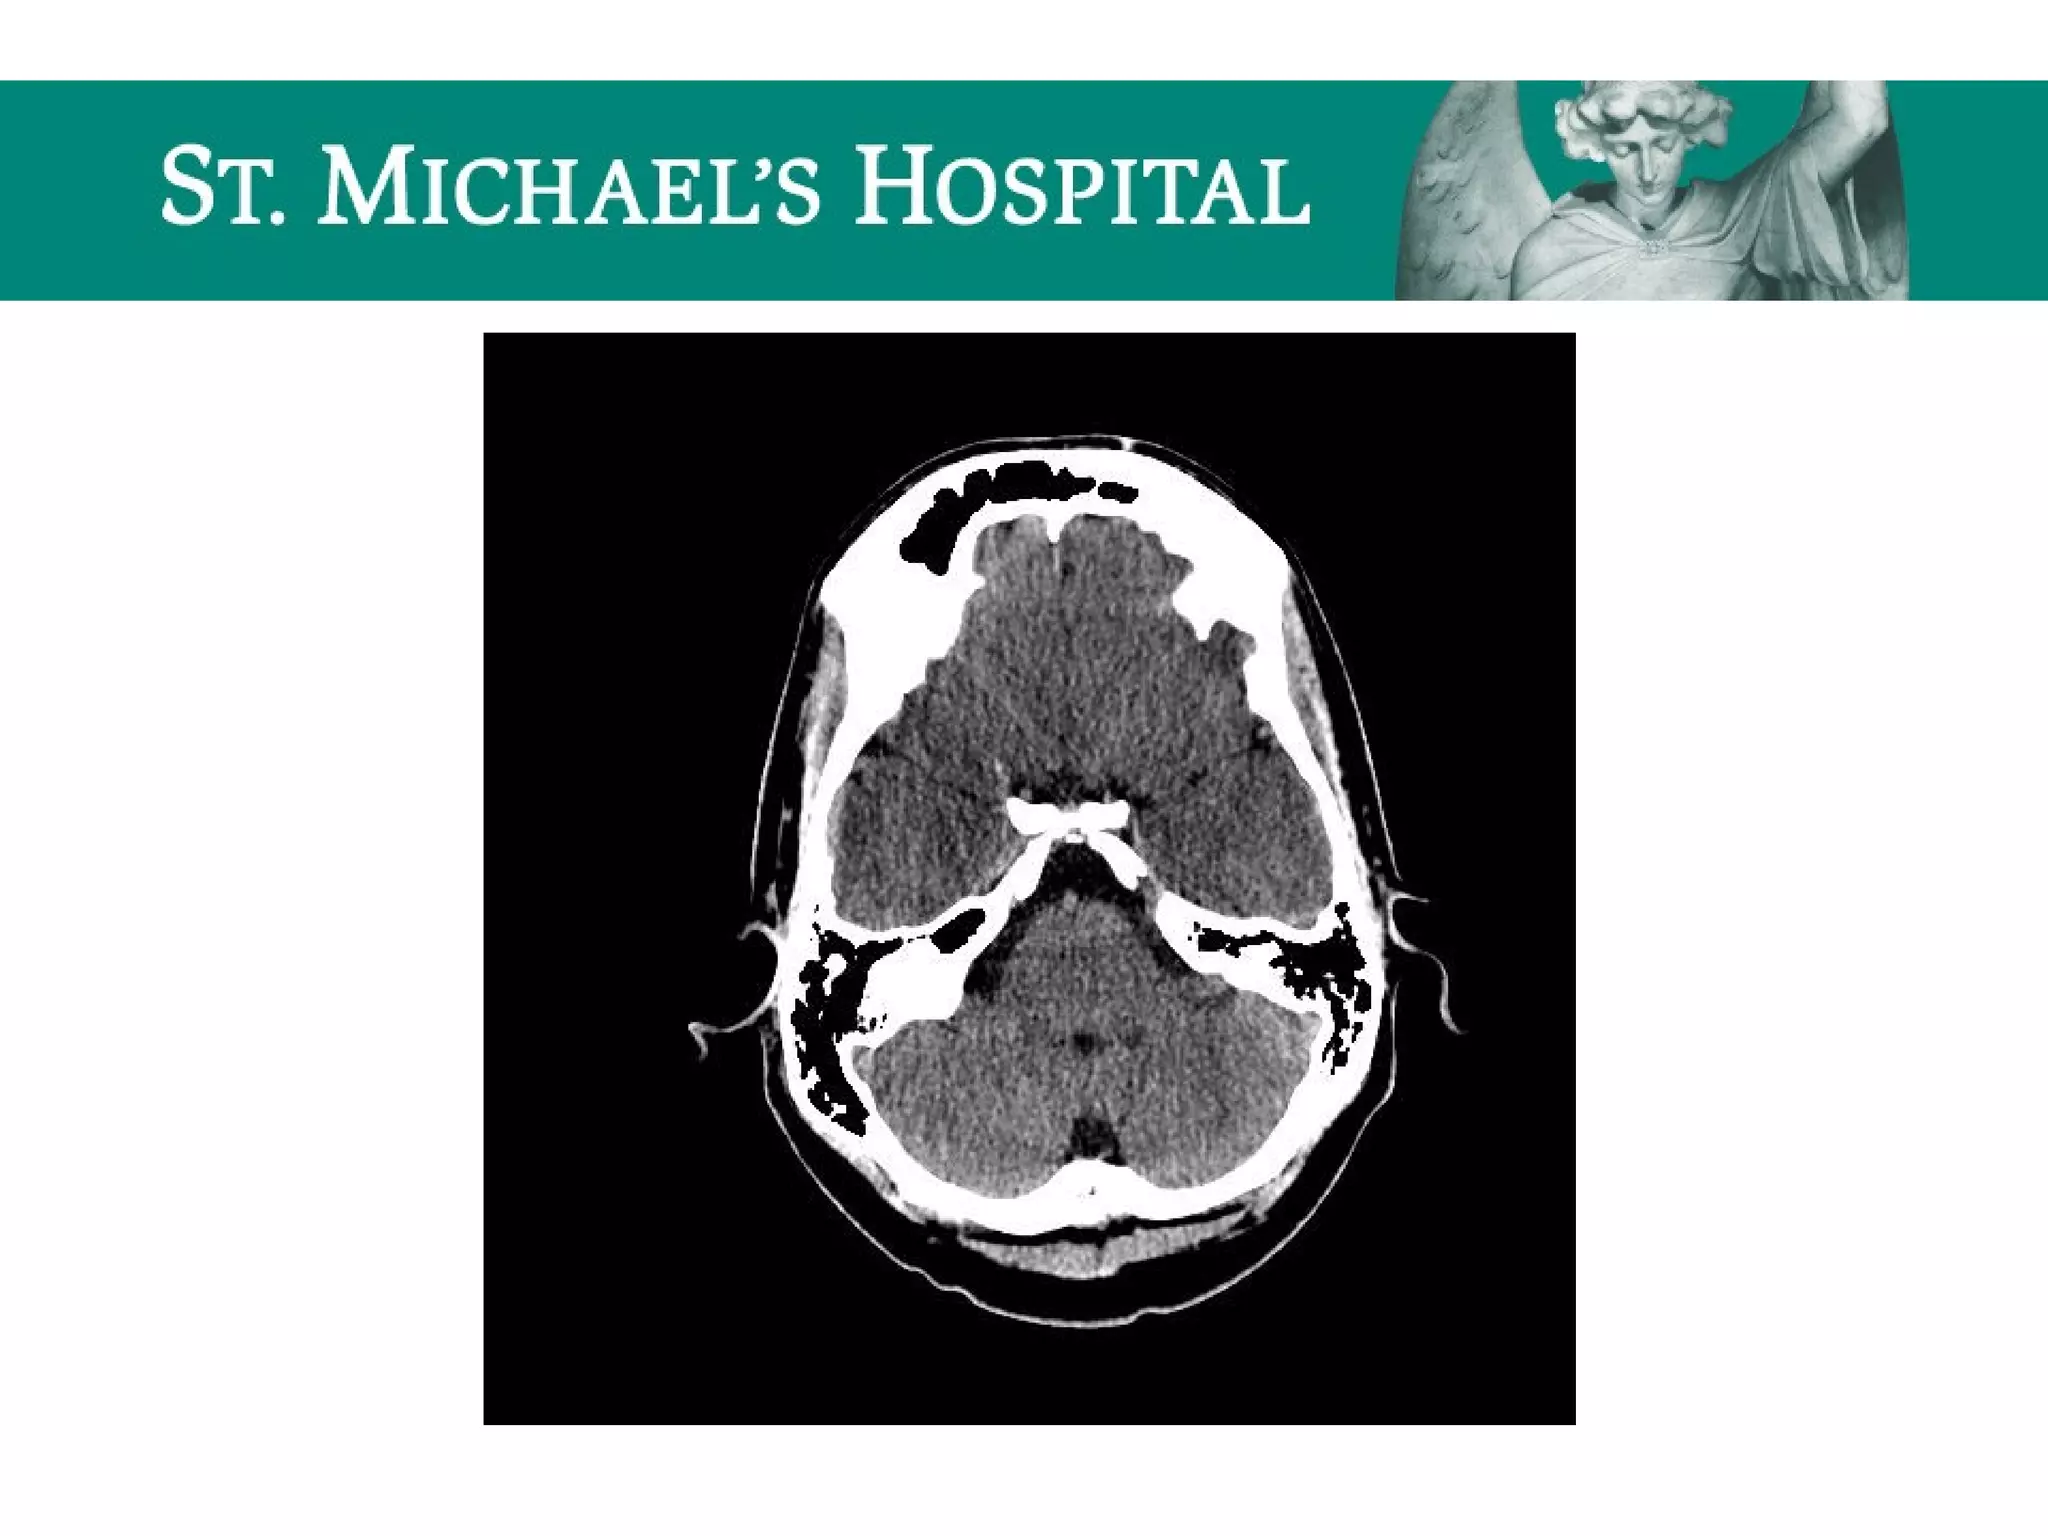

Subarachnoid Hemorrhage (SAH)

 Etiology:

 Spontaneous  ruptured aneurysm (72%),

AVM (10%), hypertensive hemorrhage

 Traumatic

 Bleeding within the subarachnoid space may

lead to obstruction of ventricular outflow of

CSF

SAH – Radiological Features

 Aneurysms (85% anterior circulation); common locations:

 ICA terminus, P.comm. junction, MCA bi/tri-furcation, A.comm, basilar tip

 Unenhanced CT:

 Highly sensitive for acute SAH (Sn~98% w/in 12 hours, 93% w/in 24 hours)

 Location of SAH correlates directly with the location of the aneurysm rupture in ~70%

– eg. A.comm. aneurysm rupture  blood in interhemispheric fissure

 Most sensitive areas for identification of SAH:

– interpeduncular cistern

– posterior aspects of Sylvian fissures

– occipital horns of lateral ventricles

Subarachnoid Hemorrhage (SAH) Etiology:  Spontaneous  ruptured aneurysm (72%), AVM (10%), hypertensive hemorrhage  Traumatic  Bleeding within the subarachnoid space may lead to obstruction of ventricular outflow of CSF

SAH – RadiologicalFeatures  Aneurysms (85% anterior circulation); common locations:  ICA terminus, P.comm. junction, MCA bi/tri-furcation, A.comm, basilar tip  Unenhanced CT:  Highly sensitive for acute SAH (Sn~98% w/in 12 hours, 93% w/in 24 hours)  Location of SAH correlates directly with the location of the aneurysm rupture in ~70% – eg. A.comm. aneurysm rupture  blood in interhemispheric fissure  Most sensitive areas for identification of SAH: – interpeduncular cistern – posterior aspects of Sylvian fissures – occipital horns of lateral ventricles